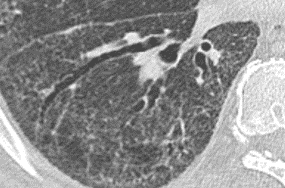

Emphysema is characterized by permanently enlarged airspaces distal to the terminal bronchiole, with destruction of alveolar walls. Emphysema is usually classified according to the part of the acinus predominantly affected. The Computed Tomography appearance of emphysema consists of focal areas or regions of low attenuation, usually without visible walls.